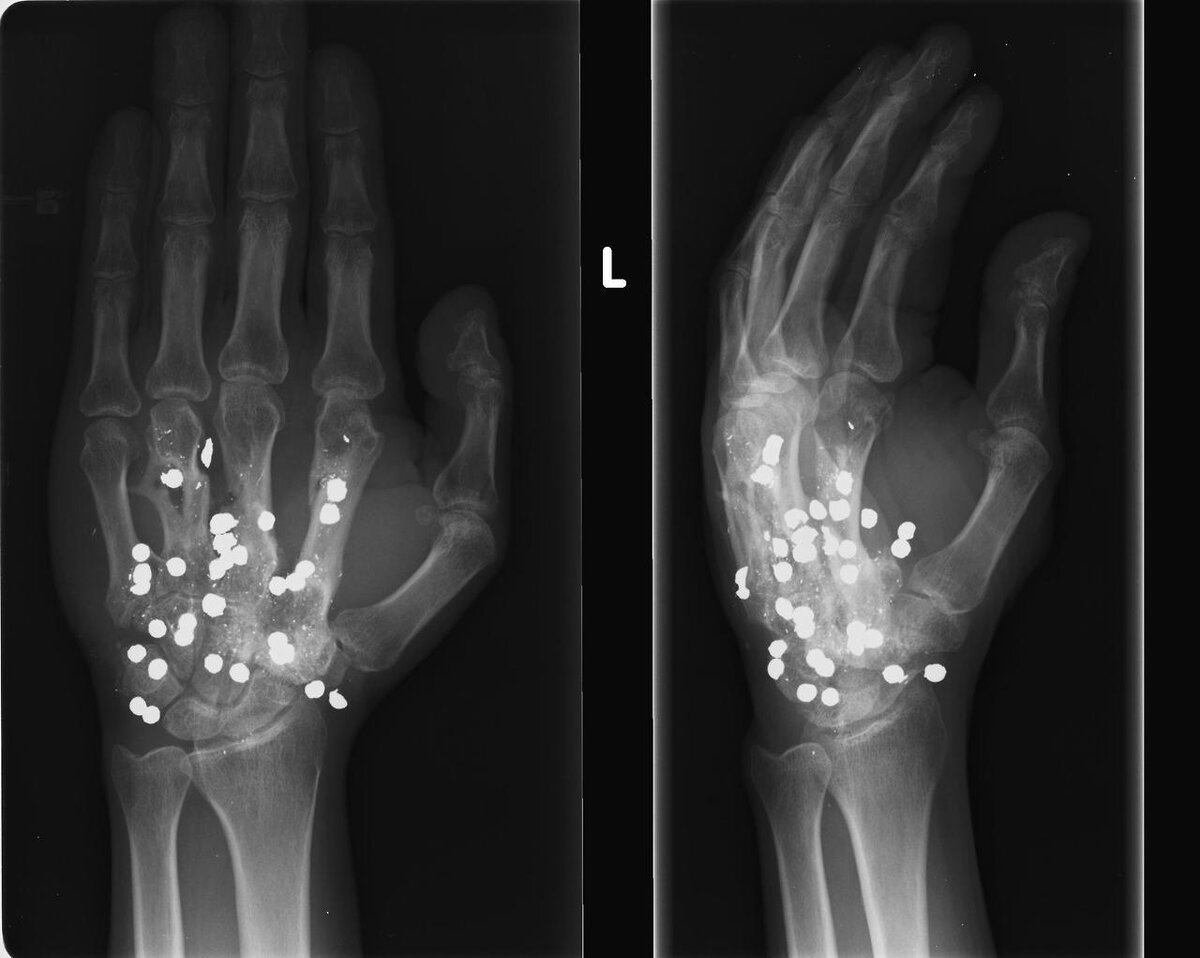

Ранение от дробовика.